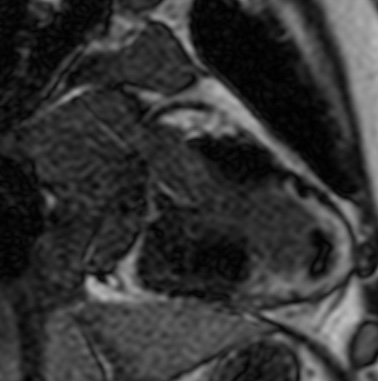

Ischemic cardiomyopathy involving LAD and partly LCX territory

There is severe thinning of the apical myocardium.

There is transmural enhancement seen in the apical, apical anterior, apical septal, apical inferior,  mid-ant septal, mid inf-septal segments ( segments17, 13,14,15,8,9). It probably represents scar tissue of non viable myocardium.